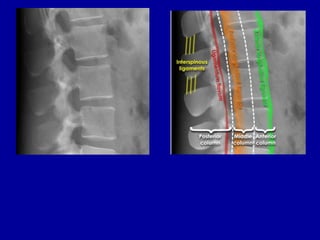

Three column model

• The Clinico-radiological assessment of thoracolumbar

spine stability is usually performed by spinal surgeons

with the help of radiologists.

• A simple model commonly used for assessment of

spinal stability is the 'three column' model. This states

that if any 2 columns are injured then the injury is

'unstable'. This theory is an over simplification if

applied to plain X-rays alone. It is important to be

aware that some injuries are not visible on X-ray and

that 2 and 3 column injuries may be underestimated as

1 or 2 column injuries respectively.

• If spinal instability is suspected on the basis of clinical

or radiological grounds then further imaging with CT

should be considered.

Three column model - Anatomy

• Anterior column = Anterior half of the

vertebral bodies and soft tissues

• Middle column = Posterior half of the

• Posterior column = Posterior elements and

soft soft tissues

• Three column model - Fracture simulation

• Injuries 1 and 2 affect one column only and are considered 'stable'

• 1 - Spinous process injury

• 2 - Anterior compression injury

• Injuries 3 and 4 affect two or more columns and are considered 'unstable'

• 3 - 'Burst' fracture

• 4 - Flexion-distraction fracture - 'Chance' type injury

Three column model - Fracture simulation